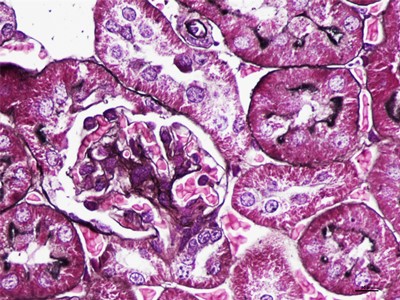

HE染色简称苏木精是是一种由碱性染液苏木精和酸性染液伊红构成的一种染色方法。是通显微镜下观察病理切片里病变的组织学形态变化来诊断疾病的,适用于胚胎学、病理学,生物医学,病理学教学与科研。HE染色对碱性染料和酸性染料亲和力都比较弱的现象称为中性。组织切片苏木素染色、分化与反蓝:将水化后的组织样本的切片使用PBS溶液浸泡清洗,每次浸泡5min,总共清洗3次。之后用移液枪吸取已经预先配置好的苏木素染色液,每个组织切片滴加100ul,充分染色10min。切片经HE染色后,要彻底脱水透明,才能用吉林中性树胶封盖。he染色对于贴壁生长细胞,胰酶消化,调整细胞浓度约1×105/ml,滴加于盖玻片上(置于6孔板中),培养相应时间后,取出细胞爬片,用PBS 洗涤3次。着色情况与组织或细胞的种类有关。切片在苏木素染液中停留过长;或切片太厚;或分化时间太短。这种情况首先镜下看看切片厚度(最佳厚度1-2层细胞核),要么重新染色,要么重新制片。染色的最终结果是:细胞核呈蓝色、胞质、肌纤维、胶原纤维和红细胞呈深浅不一样的红色,病理技术服务提醒:在进行HE染色需要染色时间,脱水,染色时间不一样,需要等 ,明确HE评判标准。